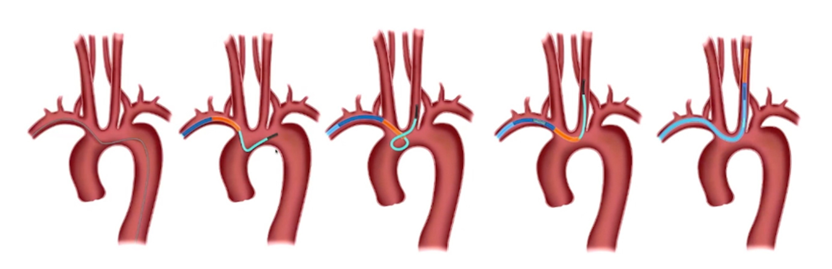

1、双侧桡动脉置入6F动脉鞘。健侧进行造影定位和观察。

患侧将0.035in泥鳅导丝通过狭窄进行小球囊扩张(3-3.5mm)建立通路,撤出球囊。

沿泥鳅导丝(不用导引导管)将7-10mm球扩支架到位,通过对侧造影铆定后球囊扩张释放。

2、输送7-10mm球扩支架时不需要导引导管,直接沿泥鳅导丝输送,球扩支架不释放时小于2.5mm,能够顺利通过桡动脉。